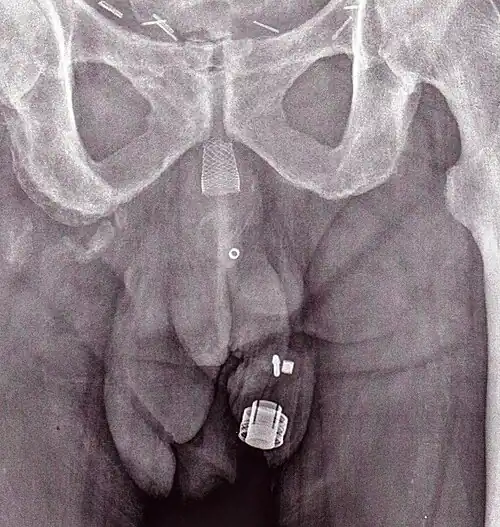

Рентгеновское изображение имплантированного ZSI 375. Устройство деактивировано — пружина сжимается ниже верхушки цилиндра. У пациента недержание мочи. -

Рентгеновское изображение имплантированного ZSI 375. Устройство активировано — пружина разжимается в верхней части цилиндра. Пациент сдерживает мочу. -